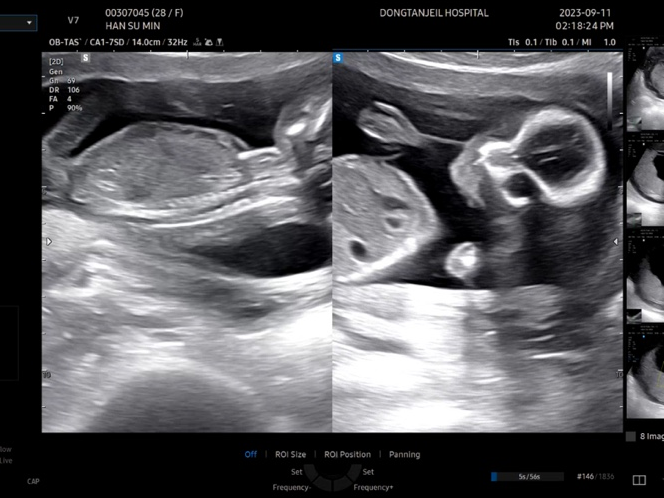

22주차 : 정밀 초음파, 초음파 잘 보는 방법, 초음파 꿀팁

22주 5일 차였던 10월 23일(월)에 정밀 초음파를 봤다. 근데 이날 처음 맞이하는 결혼기념일 이었음ㅋㅋㅋ...